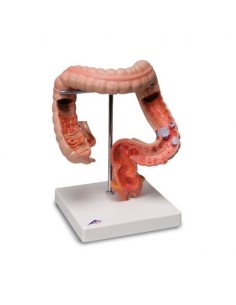

Dal cranio in 22 parti con incastri magnetici ai modelli di colonna vertebrale, da quelli di articolazioni a quelli di cuore, ogni pezzo della nostra collezione è progettato per un’immersione totale nello studio dell’anatomia umana. I nostri modelli, realizzati tramite scansioni di ossa vere, garantiscono un’esperienza tattile autentica e una fedeltà di peso quasi identica agli originali.

Essenziali per studenti e professionisti, i nostri modelli anatomici sono strumenti didattici che permettono di osservare le strutture anatomiche con precisione, eliminando la necessità di dissezioni o studi invasivi. Sono inoltre utili per spiegare ai pazienti le patologie, rendendo la comunicazione più efficace e risparmiando tempo prezioso.